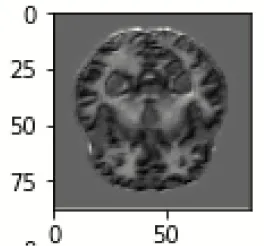

The database used in this study consists of a total of 6,200 AD images that are retrieved from the Kaggle database. It comprises grayscale images of 896 MD, 64 Mod D, 3,200 ND, and 1,966 VMD images, with a dimension of (208 × 176 × 3) pixels. The dataset for evaluation is divided in such a way that 80% of the image samples are utilized for training the model and the remaining 20% are utilized for testing the model (Filipovych et al., 2011). Figure 2 shows the database of MRI images. Table 2 shows the publicly available AD dataset.

FIGURE 2

www.frontiersin.org

Figure 2. Alzheimer's disease: (A) M.D, (B) Mod.D, (C) N.D, and (D) V.M.D.